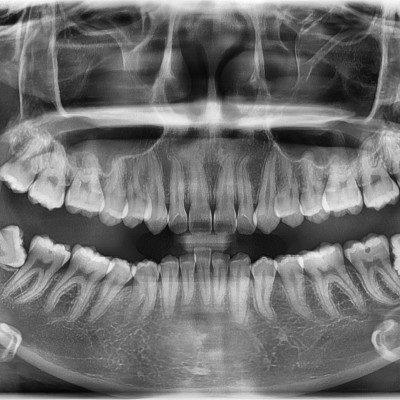

#18,28,38,48 사랑니 발치 #18,28,38,48 사랑니 발치 구강 외과 전문의가 당일 발치했습니다.

작성자 이턱이 작성일 01-28 조회 6